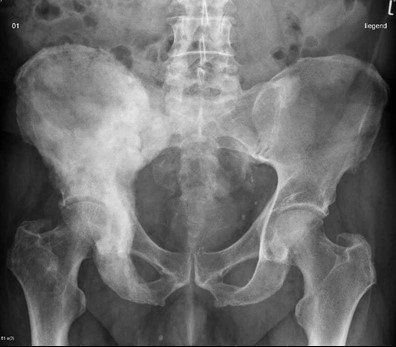

3.1. Kiểm tra hình ảnh

Thông thường, kết quả chụp X - quang sẽ cho thấy các dấu hiệu bất thường đầu tiên của bệnh paget. Hình ảnh xương có thể biểu hiện các khu vực tái hấp thu xương, mở rộng và biến dạng xương; đó là các đặc trưng của bệnh Paget.